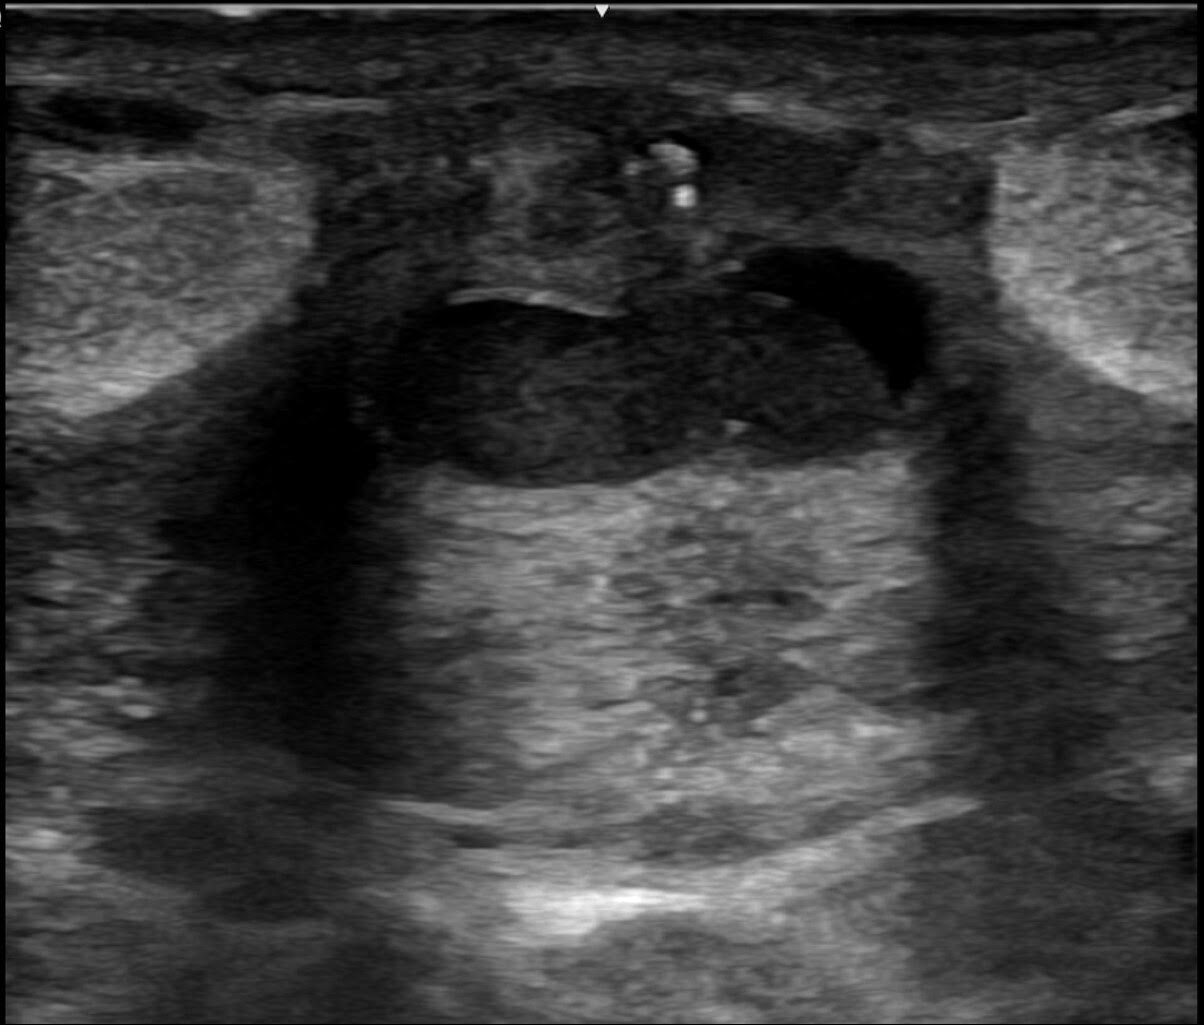

A la exploración física, presenta una induración periareolar muy dolorosa a la palpación, sin que se aprecie tumoración, eritema o calor en la mama derecha. Se solicita una ecografía mamaria (Figura 1 y Figura 2).

Figura 1. Ecografía de la mama realizada con transductor lineal de 9 Mhz. En región la periareolar de la mama derecha se observa una lesión quística bilobulada de 12 x 5 mm, con contenido ecogénico y refuerzo acústico posterior.